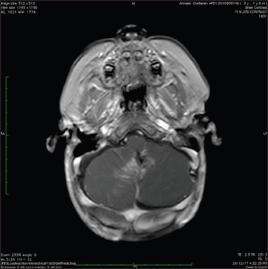

| Figure.3:High risk medulloblastoma-preoperative

The patient was taken up for surgery. He underwent suboccipital craniotomy with transvermian approach splitting the inferior aspect of the vermis. The tumor was highly vascular and noted to be involving the floor of the fourth ventricle, bilateral foramina of Luschka, and left cerebellar peduncle. Immediate postoperative imaging was not feasible. The patient underwent repeat MRI, 3 weeks postoperatively which revealed residual tumor of 2.5 cc. MRI of the spine demonstrated two focal enhancing nodules in the cervical and thoracic spine. CSF was positive for malignant cells. Molecular profiling confirmed it to be Group 3 MB with myc-amplification.

He received CSI 35 Gy in 21 fractions with posterior fossa boost of 19.8 Gy with concurrent daily carboplatin. He was commenced on chemotherapy 4 weeks' following completion of radiation with vincristine/cisplatin/CCNU and cyclophosphamide. [Figure 4] MRI post radiation in child with STR.

| Figure.4:High risk medulloblastoma-postradiation